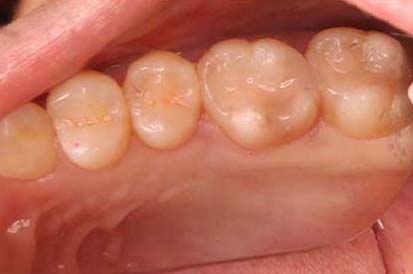

ジルコニアインレー治療の症例

| 年齢・性別 | 33歳・女性 |

|---|---|

| 主訴・治療部位 | 左上6番:定期検診にて虫歯を確認し、治療することになりました。 |

| 治療内容 | 左上6番、定期検診にて虫歯を発見しデンタル、レントゲンにて虫歯をみとめました。 虫歯の治療を行うこととなり虫歯と取りきり、詰め物の型取りを行いました。 ジルコニアの詰め物をつめ処置は終了いたしました。 |

| 治療費用 | ジルコニアインレー:44,000 (2023年1月現在) |

| 治療期間 | 1カ月 |

| リスク・副作用 | 虫歯が大きい場合、歯の神経の治療に移行することがある。 治療直後は神経の近くを削っているので痛みが出ることがある。 かみ合わせが強い方はつめ物が取れてしまう事がある。 |

| 治療方針 | 治療個所はないので引き続き定期検診でみていく。 |

| 特記事項 | ナイトガードも使えているとのことなので定期検診時にもってきていただき確認していく。 |

| 担当者所見 | 奥歯と歯の間の虫歯になった履歴が多く、詰め物が多くはお口の中に使用されている方となります。 虫歯のリスクも高いので定期検診を受けていただき今の健康な状態をキープしていきましょう。 |